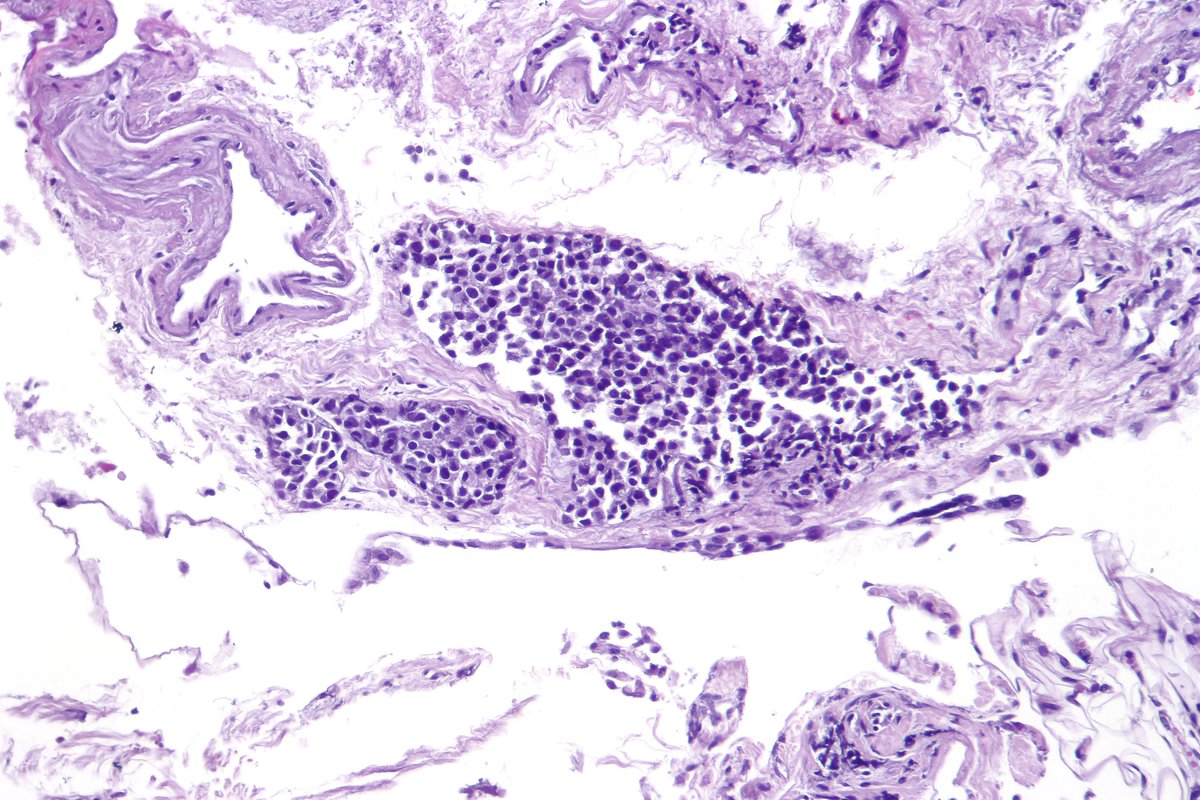

Type B2 Thymoma showing prominent large epithelial cells admixed with numerous lymphocytes. #pathology #PulmPath